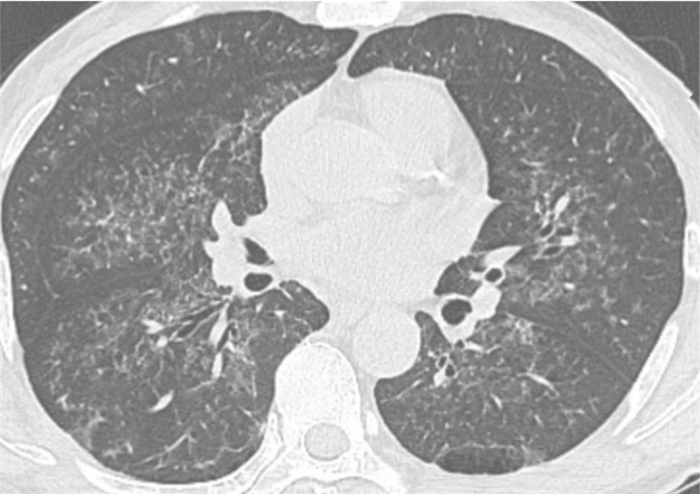

病例2 患者女性,55歲。因“發熱、咳嗽2周余”入院。體溫最高39 ℃,伴有咳嗽、咳白黏痰,活動后氣喘,自服“地塞米松、復方對乙酰氨基酚”后體溫能恢復正常,但6~12 h后體溫復升,為進一步診治收住我院血液科。既往有“慢性粒細胞白血病”7年。1年前進入“加速期”,不規則服用“伊馬替尼”治療。無粉塵暴露史。入院查體:體溫36.3 ℃,脈搏96次/min,呼吸23次/min,血壓100/64 mm Hg,指脈氧飽和度92%(吸氧3 L/min),貧血貌,右下肺可及濕啰音,腹軟,肝臟腫大,肋下2.5 cm,脾臟腫大,肋下4 cm。胸部HRCT示兩肺廣泛磨玻璃影,可見典型“鋪路石征”,呈“地圖樣”分布,伴有局部實變(右肺為著),右下肺可見較多囊狀影(圖 2)。行支氣管鏡檢查后可見渾濁米湯樣灌洗液,PAS染色(+),根據典型CT表現、氣管鏡結果及病史。診斷:(1)PAP伴感染;(2)慢性粒細胞白血病(加速期);(3)Ⅰ型呼吸衰竭。先后給予亞胺培南、萬古霉素、伏立康唑、SMZ等一系列抗感染治療后,體溫恢復正常,復查胸部HRCT提示原有實變病灶較前吸收,但“鋪路石征、地圖征”仍存在,建議患者擇期行全肺灌洗治療,患者后至外院治療并失訪。